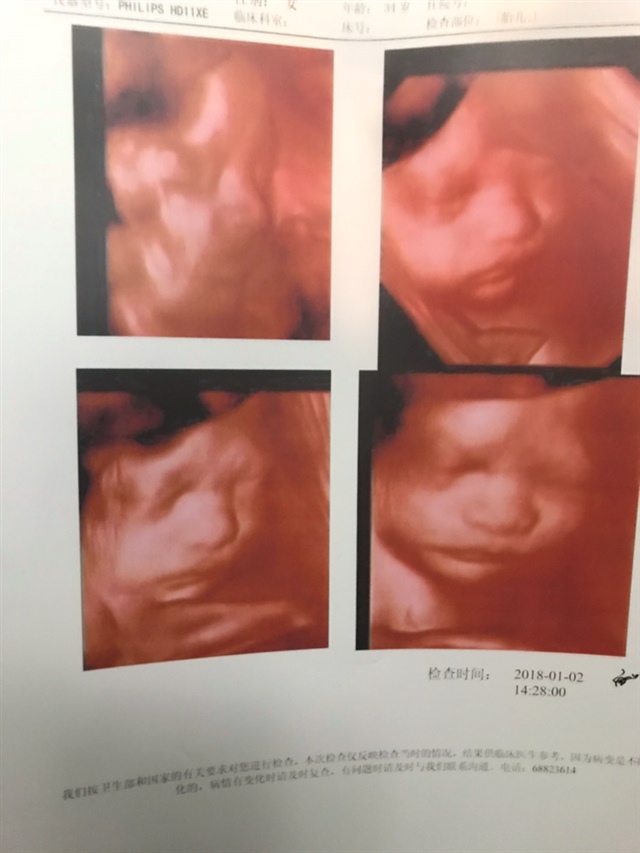

孕14周+0天

每次给他照照片,就躲,不是漏上脸就是只漏嘴巴,搞笑的是看不到他,看到了还在打哈欠没睡好的样子,第二次漏个嘴巴脸手挡住微笑着,把我们逗了啦,医生说鼻子很挺